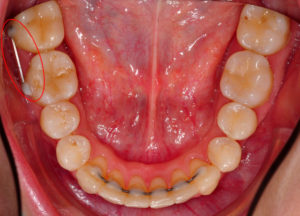

После снятия брекетов всегда необходимо установить ретейнер. На фото вы видите основные типы ретейнеров.

Ретейнеры после брекетов на зубах нижней челюсти

Зафиксированные ретейнеры после снятия брекетов. Для фиксации использовался фотокомпозитный материал.